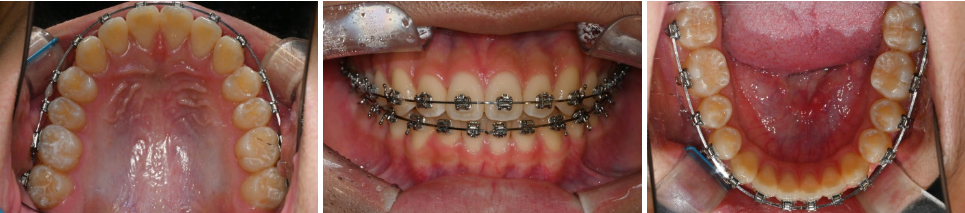

치료과정

24.05.02

24.10.11

24.07.05